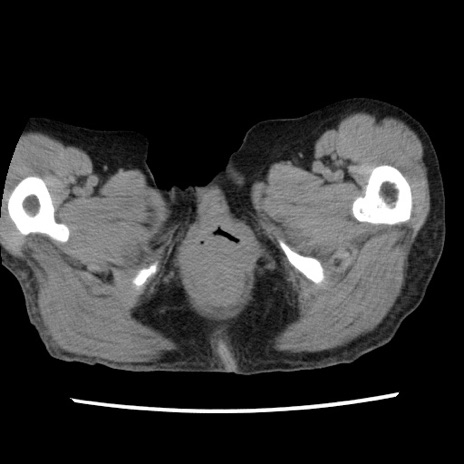

症例1(横断像)

【症例】80歳代女性

【主訴】腹痛

【現病歴】8時間前から腹痛あり来院。

【既往歴】糖尿病、脂質異常症、子宮体癌にて子宮全摘術

【身体所見】意識清明・会話良好だが腹痛で苦悶様、全腹部にわたって反跳痛と圧痛あり

【データ】WBC 13600、CRP 0.14、LDH 224、CK 90